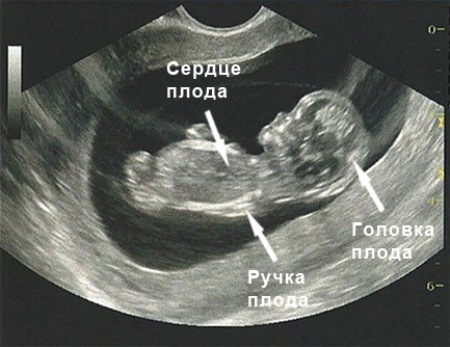

На девятой неделе хвостик малыша трансформируется в копчик, а конечности, которые уже начали формироваться, продолжают удлиняться. Кроха уже может шевелить ими, сжимать кисти в кулак и разжимать их. Все эти удивительные изменения можно увидеть на ультразвуковом исследовании, однако мама пока не ощущает движений своего малыша.

В четырехкамерном сердце плода продолжается формирование клапанов. Биение маленького сердечка можно зафиксировать с помощью аппарата УЗИ – на этом сроке оно сокращается с частотой 150–170 ударов в минуту.

На девятой неделе беременности может возникнуть необходимость в проведении ультразвукового исследования, которое поможет оценить состояние плода и уточнить срок беременности. На данном этапе УЗИ уже позволяет наблюдать, как малыш активно двигает ручками и ножками в моменты бодрствования, а также фиксировать его сердечные сокращения. В этот период частота сердцебиения плода составляет от 150 до 170 ударов в минуту.